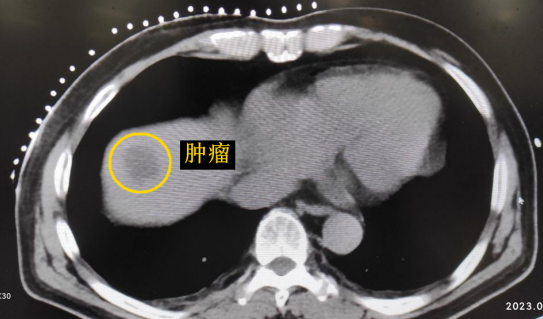

患者老年男性,曾于2021年行結(jié)腸癌手術(shù)。幾月前,發(fā)現(xiàn)肝臟轉(zhuǎn)移瘤,但沒(méi)有干預(yù)。近期CT顯示該轉(zhuǎn)移瘤明顯增大,并發(fā)現(xiàn)另一處轉(zhuǎn)移灶。

影像診療科陳寶瑩主任團(tuán)隊(duì)評(píng)估后指出,較大的腫瘤位于肝頂部緊貼膈肌,如果繼續(xù)發(fā)展,腫瘤很可能突破肝包膜侵犯到膈肌,建議及時(shí)干預(yù)。病變緊臨膈肌,如果要完全消融,膈肌損傷的可能性就比較大,與其他局部治療方式比較,冷凍消融對(duì)周?chē)K器、血管及神經(jīng)損傷的可能性較小、安全性更高、患者疼痛感較輕,建議通過(guò)CT精準(zhǔn)引導(dǎo)下經(jīng)皮微創(chuàng)冷凍消融治療。

CT精準(zhǔn)定位腫瘤